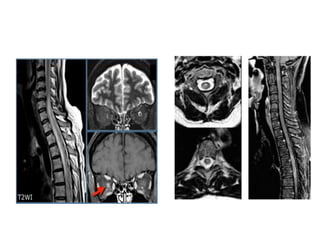

• Neuromyelitis optica (Devic type) -is a syndrome of acute

onset of optic neuritis and transverse myelitis that develop

at approximately the same time and dominate the clinical

picture

• . This condition has a different pathogenesis from most of

the other MS types related to the fact that demyelination

is antibody dependent and complement mediated

• . Approximately 50% of these patients die within several

months

• . The relationship of Devic syndrome to MS is

controversial; indeed, other acute demyelinating

disorders, including acute disseminated

encephalomyelitis, can affect optic nerves and spinal cord

• MS lesions of the spinal cord are usually found in

combination with lesions in the brain; however,

5% to 24% of cases can be found in isolation

• MR studies have shown that cord abnormalities

may be found in approximately 75% of MS

patients and in an even higher proportion of

patients with spinal cord symptoms

• Most lesions are found in the cervical region

• Axial T2-weighted images demonstrate the

typical peripheral location of MS lesions commonly

the dorsolateral aspect of the cord, where pial veins

are adjacent to white matter .

• Involvement of both gray and white matter by MS

plaques can be seen.

• Gadolinium contrast administration frequently

demonstrates enhancement of acute spinal cord

lesion

• The most typical enhancement pattern in

demyelinating spinal cord lesions is a peripheral

ringlike enhancement, although this is not always

seen

• Enhancing MS plaques can be virtually

indistinguishable from neoplastic lesions and other

inflammatory lesions of the spinal cord particularly

when the spinal cord is enlarged due to edema.

• Therefore, clinical correlation and often serial

follow-up scanning are necessary to formulate a

specific diagnosis,